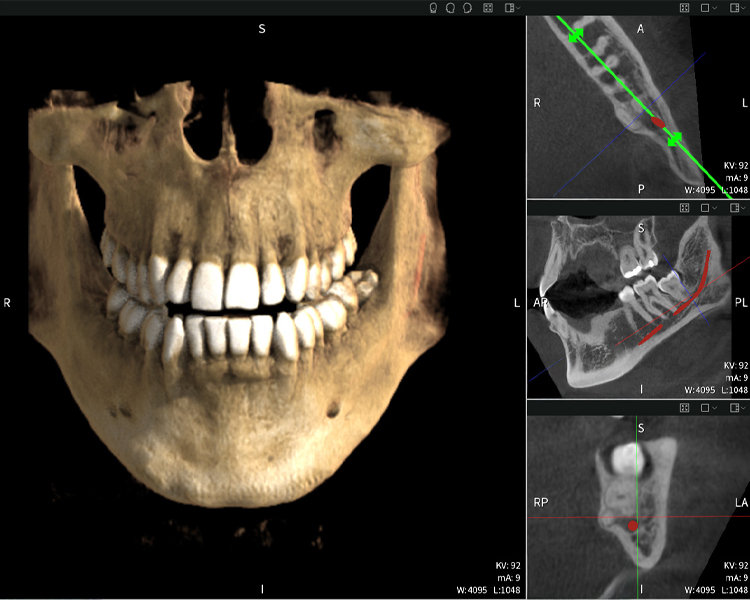

A continuación encontrarás un caso del Dr. med. dent. Oliver A. Centrella, en el cual las imágenes CBCT obtenidas con Seethrough Max proporcionaron información crucial sobre la anatomía compleja y la relación crítica entre las muelas del juicio y el nervio alveolar inferior. En este caso, existe una indicación para la extracción quirúrgica de las muelas del juicio.

Figura a: Resultados de imagen de Seethrough Max, sobre un fondo negro.

Figura a

• Arriba a la izquierda: Corte axial de la mandíbula izquierda (región 38) que muestra el nervio alveolar inferior (en rojo) en proximidad a las raíces del diente 38.

• Arriba a la derecha: Reconstrucción 3D de toda la mandíbula para orientación. El nervio alveolar inferior marcado en rojo ilustra su ubicación dentro del hueso mandibular.

• Abajo a la izquierda: Vista sagital de la mandíbula (región 38), destacando la estrecha relación espacial entre las raíces y el conducto del nervio.

• Abajo a la derecha: Vista coronal de la mandíbula (región 38), crucial para evaluar la posición espacial de las raíces en relación con el nervio.